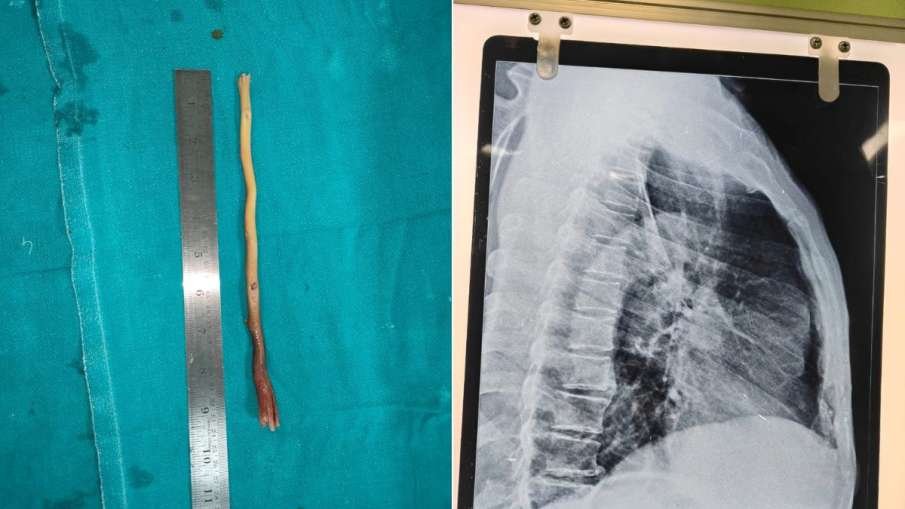

ओडिशा: गंजाम जिले के नाटंगा गांव से एक हैरान करने वाली घटना सामने आई है। यहां 80 वर्षीय कामराजू नायक रोज की तरह दांत साफ कर रहे थे, तभी गलती से दातून का लगभग 9 इंच लंबा टुकड़ा उनके गले से फिसलकर भोजन नली (फूड पाइप) में फंस गया। इसके बाद उन्हें सीने और पेट में तेज दर्द होने लगा और खाना निगलना तक मुश्किल हो गया। हालत बिगड़ने पर परिवार ने उन्हें कई जगह दिखाया लेकिन राहत नहीं मिली।

आखिरकार परिजन उन्हें ब्रह्मपुर के MKCG मेडिकल कॉलेज लेकर पहुंचे, जहां ENT विशेषज्ञ डॉ. संजीत कुमार मिश्रा और उनकी टीम ने जांच के बाद तुरंत ऑपरेशन का फैसला लिया। बुजुर्ग की उम्र और हाई ब्लड प्रेशर जैसी समस्याओं के कारण सर्जरी जोखिम भरी थी। डॉक्टरों ने ‘एसोफोगास्कोपी’ तकनीक का उपयोग कर सावधानीपूर्वक दातून को बाहर निकाला।

सर्जरी पूरी तरह सफल रही और अब कामराजू नायक की हालत स्थिर है। डॉक्टरों का कहना है कि यह घटना बताती है कि उम्रदराज लोगों को दातून जैसी कठोर चीजों से दांत साफ करते समय ज्यादा सावधानी बरतनी चाहिए।